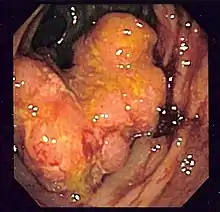

During a colonoscopy, biopsies of the colon are often taken to confirm the diagnosis. Certain characteristic features of the pathology seen point toward Crohn's disease; it shows a transmural pattern of inflammation, meaning the inflammation may span the entire depth of the intestinal wall.[1]

Granulomas, aggregates of macrophage derivatives known as giant cells, are found in 50% of cases and are most specific for Crohn's disease. The granulomas of Crohn's disease do not show "caseation", a cheese-like appearance on microscopic examination characteristic of granulomas associated with infections, such as tuberculosis. Biopsies may also show chronic mucosal damage, as evidenced by blunting of the intestinal villi, atypical branching of the crypts, and a change in the tissue type (metaplasia). One example of such metaplasia, Paneth cell metaplasia, involves the development of Paneth cells (typically found in the small intestine and a key regulator of intestinal microbiota) in other parts of the gastrointestinal system.[149][150]

Diagnosis

The diagnosis of Crohn's disease can sometimes be challenging,[28] and many tests are often required to assist the physician in making the diagnosis.[32] Even with a full battery of tests, it may not be possible to diagnose Crohn's with complete certainty; a colonoscopy is approximately 70% effective in diagnosing the disease, with further tests being less effective. Disease in the small bowel is particularly difficult to diagnose, as a traditional colonoscopy allows access to only the colon and lower portions of the small intestines; introduction of the capsule endoscopy[151] aids in endoscopic diagnosis. Giant (multinucleate) cells, a common finding in the lesions of Crohn's disease, are less common in the lesions of lichen nitidus.[152]

Endoscopic image of Crohn's colitis showing deep ulceration